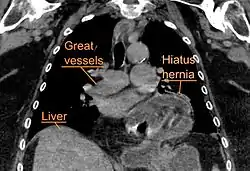

A large hiatal hernia as seen on CT imaging